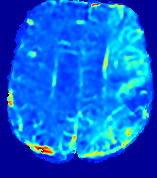

LesionRefer to captionRefer to captionRefer to captionRefer to captionRefer to captionRefer to caption𝐕rgbsubscript𝐕𝑟𝑔𝑏{\bf{V}}_{rgb}Refer to captionRefer to captionRefer to captionRefer to captionRefer to captionRefer to caption𝐕2subscriptnorm𝐕2{\|\bf{V}}\|_{2}Refer to captionRefer to captionRefer to captionRefer to captionRefer to captionRefer to captionRefer to caption3.53.53.52.82.82.82.12.12.11.41.41.40.70.70.70.00.00.0(mm/s)𝑚𝑚𝑠(mm/s)D𝐷DRefer to captionRefer to captionRefer to captionRefer to captionRefer to captionRefer to captionRefer to caption0.0200.0200.0200.0160.0160.0160.0120.0120.0120.0080.0080.0080.0040.0040.0040.0000.0000.000(mm2/s)𝑚superscript𝑚2𝑠(mm^{2}/s)Slice #1Slice #2Slice #3Slice #4Slice #5Slice #6

Figure 3: PIANO feature maps for one stroke patient, where the lesion is located in the left hemisphere. Top row: segmented stroke lesion region (white) on different slices, obtained from ISLES 2017. The corresponding slices for the PIANO feature maps are shown in the following rows.

For a better insight into an estimated velocity field 𝐕𝐕{\bf{V}} and diffusion field 𝐃𝐃{\bf{D}}, we compute the following maps: (1) 𝐕rgbsubscript𝐕𝑟𝑔𝑏{\bf{V}}_{rgb}: Color-coded orientation map of 𝐕=(Vx,Vy,Vz)T𝐕superscriptsuperscript𝑉𝑥superscript𝑉𝑦superscript𝑉𝑧𝑇{\bf{V}}=(V^{x},V^{y},V^{z})^{T}, obtained by normalizing 𝐕𝐕{\bf{V}} to unit length and mapping its 3 components to red, green, blue respectively; (2) 𝐕2subscriptnorm𝐕2\|{\bf{V}}\|_{2}: 222 norm of 𝐕𝐕{\bf{V}}; (3) D𝐷D: scalar field in Eq. 5.

Fig. 3 and Fig. 4 show the PIANO feature maps estimated from two ISLES 2017 patients: all are highly consistent with the lesion in both cases. Details of the blood flow trajectories are revealed in 𝐕rgbsubscript𝐕𝑟𝑔𝑏{\bf{V}}_{rgb} by the ridged patterns and the sharp changes of colors in the unaffected (right) hemisphere, while the flat patterns appearing within the lesion provide little directional information about the velocity and indicate low velocity magnitudes. Velocity magnitudes are more directly visualized via 𝐕2subscriptnorm𝐕2\|{\bf{V}}\|_{2}, from which one can easily locate the lesion where 𝐕2subscriptnorm𝐕2\|{\bf{V}}\|_{2} is low. D𝐷D also indicates lower diffusion values in the lesion, though with less contrast potentially due to the fact that it captures the accumulated effect of CA diffusion at the voxel-level.